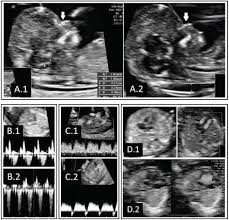

Ultrasound Images Of A Normal Fetus A And A Fetus With Trisomy 21 B Download Scientific Diagram

A Review Of Ultrasound Imaging Techniques For The Detection Of Down Syndrome Sciencedirect

Down syndrome is a genetic disorder caused when abnormal cell division results in an extra full or partial copy of chromosome 21. This test is done between 15 and 20 weeks of pregnancy. In 2011 a nicely done experiment by Marshall et al showed that regular hamstring stretching substantially increased range of motion in normal university kids95 Specifically after a 4-week stretching program consisting of 4 hamstring and hip stretches performed 5 times per week their range increased about 16 or 20. Down syndrome is a genetic disorder caused when abnormal cell division results in an extra full or partial copy of chromosome 21. In Down syndrome the nuchal translucency measurement is abnormally large as shown on the left in the ultrasound image of an 11-week fetus. How is a dating scan performed. The 20-Week Anatomy Scan May 2017.